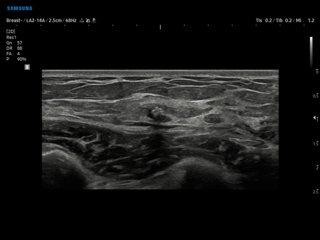

Atlas of ultrasound images - mammology

In the section "Mammology" of atlas the results of ultrasonic examinations of diseases of the breast are represented. Here you can see ultrasound images: the mammary gland in the norm, cyst, node, etc.